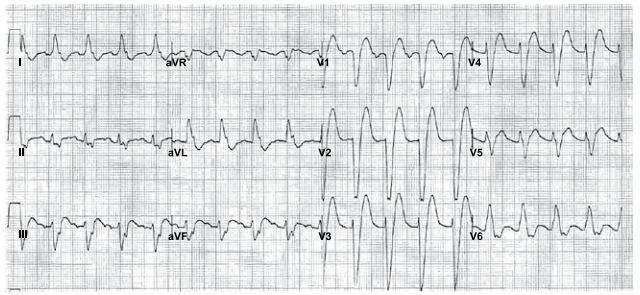

Durante o atendimento de vítima em parada cardiorrespiratória, foi realizada, no segundo ciclo, uma desfibrilação com 200 J e administrado 1 mg de adrenalina. Após manutenção das manobras de ressuscitação cardiorrespiratória e nova análise do ritmo (registro a seguir), foi realizada uma nova desfibrilação.

Homem, 77 anos, hipertenso e diabético, em uso regular de losartana, hidroclorotiazida e metformina, queixa-se de palpitação e pré-síncope nos últimos 3 meses. O exame físico é normal e o ecocardiograma mostra função biventricular preservada e ausência de alterações da contratilidade segmentar. O eletrocardiograma dinâmico, durante exacerbação dos sintomas, está apresentado a seguir.

Após internação e monitorização, houve rebaixamento súbito do nível de consciência. A paciente ficou desacordada, sem responder a estímulos verbais ou dolorosos e sem apresentar pulsos centrais e movimentos respiratórios. Uma tira de ritmo cardíaco obtida nesse momento está ilustrada a seguir.